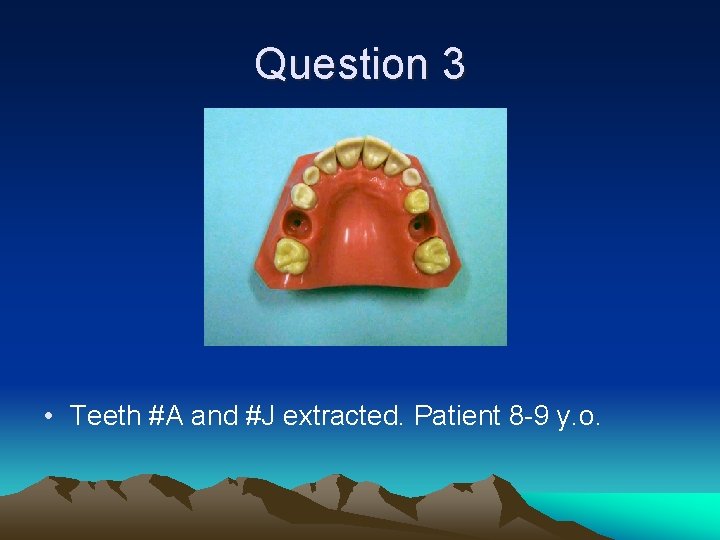

Question 3 • Teeth #A and #J extracted. Patient 8 -9 y. o.

Question 3 • Nance #3 -#14 • Can be removed when #4 and #13 erupt-around age 12